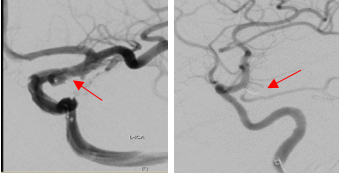

LIVS支架辅助栓塞后造影显示微小动脉瘤不显影,分支通畅

双微管栓塞后显示右侧后交通段动脉瘤不显影,分支通畅